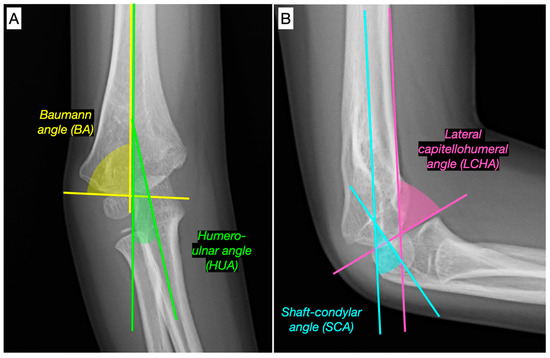

- Goldfarb, C.A.; Patterson, J.M.M.; Sutter, M.; Krauss, M.; Steffen, J.A.; Galatz, L. Elbow radiographic anatomy: Measurement techniques and normative data. J. Shoulder Elb. Surg. 2012, 21, 1236–1246. [Google Scholar] [CrossRef]

- Shank, C.F.; Wiater, B.P.; Pace, J.L.; Lee, J.; Thomas, J.; Schmale, G.; Bittner, G.; Bompadre, V.; Stults, J.; Krengel, W. The lateral capitellohumeral angle in normal children: Mean, variation, and reliability in comparison to Baumann’s angle. J. Pediatr. Orthop. 2011, 31, e266–e271. [Google Scholar] [CrossRef] [PubMed]

| CA | −20 (−18 to −26) | −6 (−4 to −9) | −16 (−18 to −9) | <0.001 |

| HUA | −19 (−15 to −29) | −8 (−1 to −10) | −16 (−19 to −12) | <0.001 |

| BA | 90 (87 to 100) | 81 (76 to 83) | −11 (−17 to −7) | <0.001 |

| SCA | 29.8 (24.3 to 36.2) | 38.5 (38.1 to 40) | 7.5 (3.3 to 13.8) | <0.001 |

| LCHA | 61.6 (54 to 64.1) | 56.7 (54.6 to 57.3) | −4.8 (−6.8 to 0.6) | 0.018 |